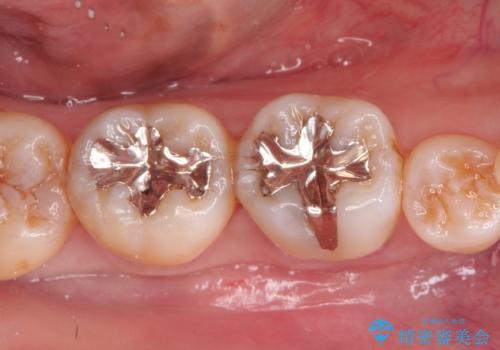

メタルインレーからセラミックインレーへ

- メタルインレーによる審美障害を主訴に来院されました。

セラミックインレーに治療を行っております。